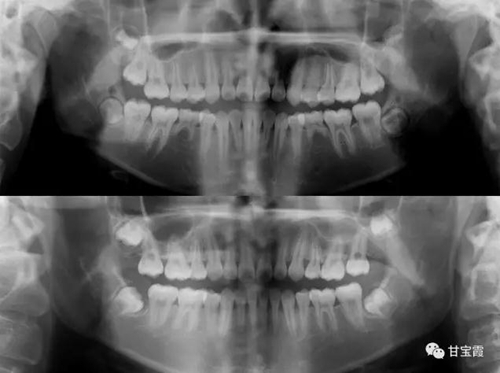

我有個朋友的小女孩前牙不齊、有點突,要求矯正。經(jīng)過臨床檢查和X診斷,發(fā)現(xiàn)先天缺失兩顆下頜第二雙尖牙。

1.jpg

2.jpg

下面這兩張X片子就是矯正前后的對比,看不出下頜缺牙

5.jpg